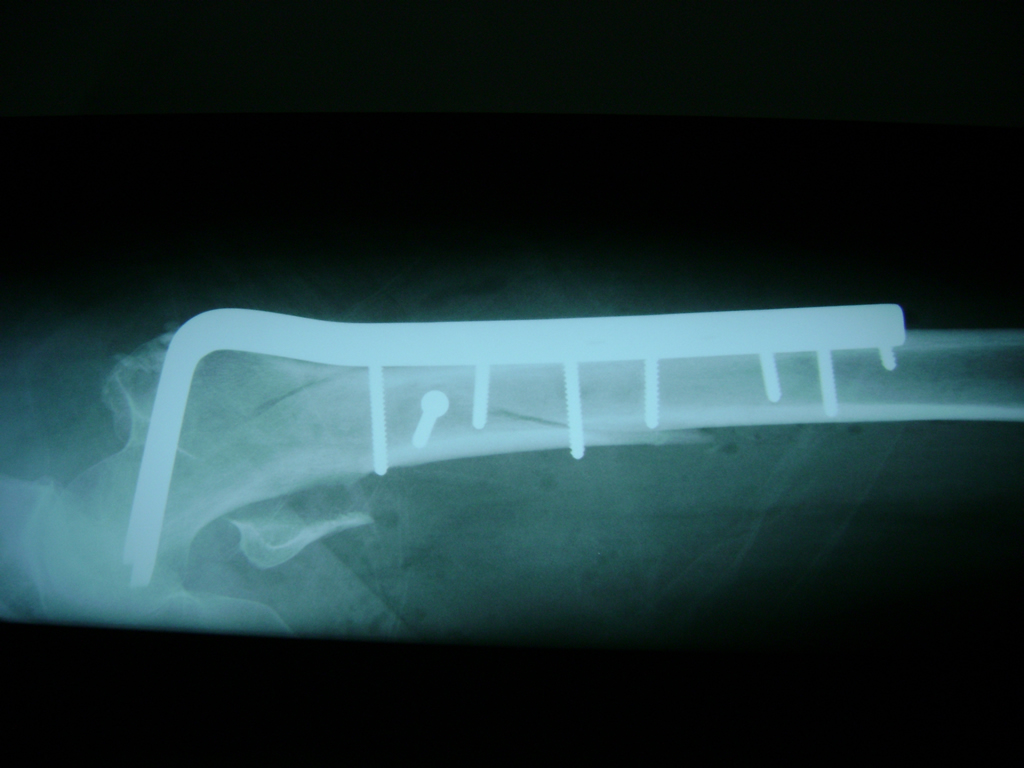

La cirugía de fractura de cadera se realiza para reparar una ruptura en la parte superior del hueso del muslo. Este hueso se denomina fémur.

A menudo se recomienda la cirugía para reparar la fractura debido a dichos riesgos.